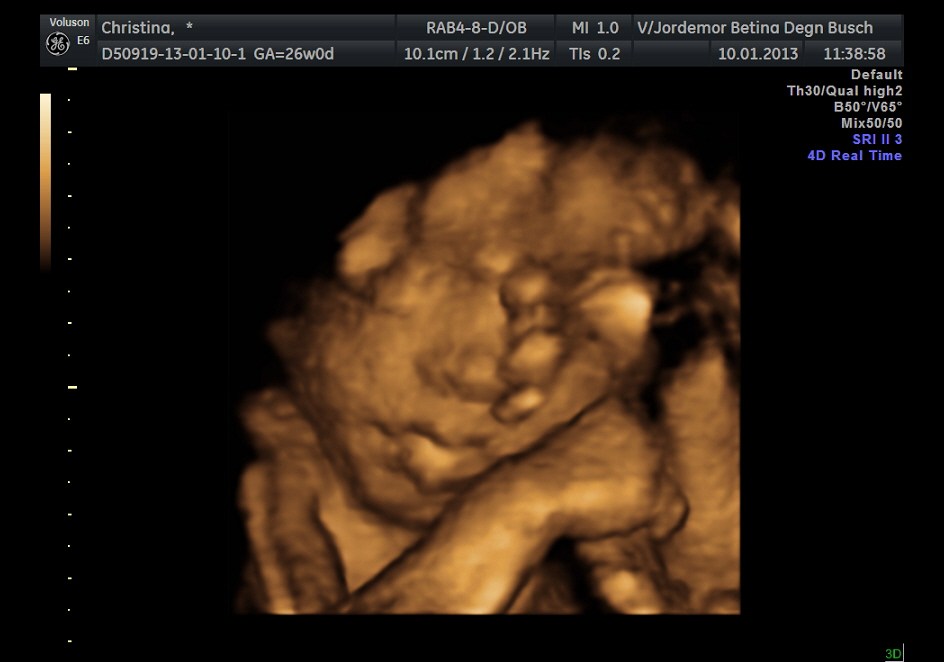

hun gav en lille smags prøve på 3d billeder da jeg nævnte at vi vil komme ind til hende når vi ramte uge 28+..

Vedhæftede fotos (klik for at se i fuld størrelse)